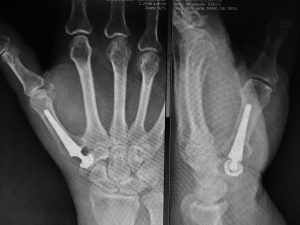

🔹 Osteotomías correctivas: se realizan cortes controlados en el hueso para corregir su alineación y fijarlos con placas o clavos.

🔹 Cirugía guiada por imagen: mayor precisión, menor invasión y mejor planificación.

Cada caso es valorado por nuestro equipo de traumatología y cirugía ortopédica, que realiza un estudio radiológico completo y planifica el tratamiento más adecuado según la edad, la localización de la deformidad y el estado general del paciente. Contamos con experiencia en cirugía infantil y de adultos, así como en técnicas de corrección progresiva y procedimientos reconstructivos complejos.